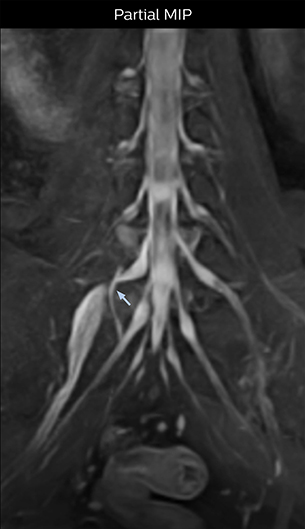

At Northern Fukushima Medical Center in Japan, excellent MRI visualization of nerves helps support confident diagnoses and informs surgical treatment decisions for patients with lower limb symptoms. MRI technologist Tanji and orthopedic surgeon Dr. Yabuki share how direct nerve visualization with the 3D NerveVIEW method adds information when diagnosing atypical herniations. The additional insights changed their way of working and benefit their patient care, as illustrated by some clinical examples.

“In patients with lower extremity neurological symptoms, NerveVIEW helps us to determine the disease matching the patient’s symptoms by directly visualizing the nerves. We use the sequence mainly, when there is suspicion of intraforaminal stenosis, extraforaminal stenosis or lateral disc herniation, which is often based on routine T2- and T1-weighted images. Additionally, the excellent depiction of the course of nerves makes NerveVIEW a good navigator when applying treatment such as block therapy or surgery.”

“In such case, we would then browse through axial T2-weighted MR images slice by slice and mentally reconstruct the actual situation based on both radiculography and MRI. Fortunately, NerveVIEW can now very well show nerve courses and presence of nerve compression or edema in one single image series.” “We have often seen NerveVIEW directly depict details of the nerve compression that were not observed by radiculography. Therefore, we think that with NerveVIEW we can reduce the number of invasive examinations, especially for some patients with lumbar plexus symptoms.”

The key concept in MR neurography, Dr. Yabuki stresses, is the ability to directly visualize spinal nerves, versus inferring the presence of pathology indirectly. “Before NerveVIEW, we estimated compression of the nerve by looking for the presence or absence of fat signal on other MR images,” he says.

“For example, in sagittal images, when the presence of fat is observed in the intervertebral foramen, it suggests that there is a margin around the nerve. Similarly, the absence of fat indicates that the nerve is being compressed. So, we used to deduce nerve compression indirectly. With NerveVIEW, however, we can observe the condition of the nerves directly, regardless of the presence or absence of fat. We always prefer such direct observation of anatomy over having to make an inference about it.”

“Although symptoms of typical disc herniation and atypical hernia are very similar, the actual site of herniation is different. It is therefore important to characterize the nerve’s condition both inside and outside of the intervertebral foramina. “Conversely, if we see no abnormality in NerveVIEW, we can assume at least that there is no severe condition that requires surgery. Like this, it can help us avoid unnecessary surgery. NerveVIEW can have a tremendous impact in this way.”

“NerveVIEW is really useful for those cases where a nerve disorder is strongly suspected based on the clinical examination but our regular MRI images do not show any findings. These atypical herniations and spinal canal stenosis, occurring in 5% to 15% of the total lumbar herniation/stenosis cases are our main target when using NerveVIEW,” says Dr. Yabuki.